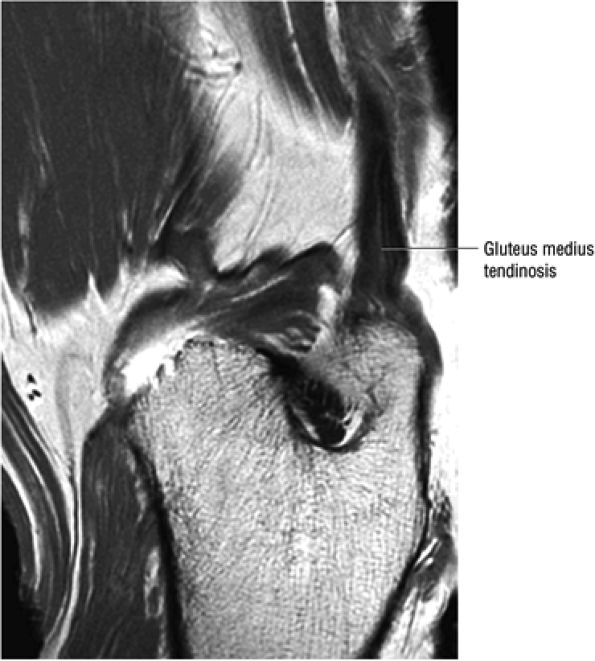

FIGURE 3.16 ● GLUTEUS MEDIUS The gluteus medius abducts and medially rotates the thigh when the extremity is extended.

FIGURE 3.30 ● Normal sagittal anatomy of the hip. (A and B) On medial sagittal images, the course of the obturator internus, piriformis, and the adductor muscles can be followed and analyzed for strain injury or tears. (C and D) Tendinosis and tears of the common hamstring tendon origin on the ischial tuberosity are optimally viewed at this location and are extremely common in middle aged and elderly patients. (E and F) Although thinning and fraying of the articular cartilage can occur anywhere in the joint, chondral degeneration is most commonly seen first in the anterior superior quadrant, often accompanied by anterior labral tears, subchondral edema, and cystic change in the anterior acetabulum. When any one of these findings is present, a careful search for the others should be performed. (G and H) Linear tears of the anterior labrum can be mimicked by fluid filling a normal recess between the anterior labrum and the anterior joint capsule. Imaging in the axial and coronal planes is used to distinguish between a true tear and the normal recess, since a tear is visualized and confirmed in the axial and coronal planes, whereas a recess is only seen prominently in the sagittal plane. (K and L) The gluteus medius and minimus tendons have been referred to as the “rotator cuff” of the hip. The gluteus medius tendon inserts posteriorly on the greater trochanter, and the gluteus minimus tendon inserts anterolaterally on the greater trochanter. (I and J) Loose bodies commonly lodge in the joint recesses anterior and posterior to the femoral neck (deep to the iliofemoral and ischiofemoral ligaments). They are commonly seen (particularly in the sagittal plane) in patients with chondral degeneration. (M and N) Acute tears of the gluteus medius and minimus often mimic symptoms of a proximal femoral fracture. Chronic partial tears and tendinosis are frequently associated with trochanteric bursitis, and are common in middle-aged and elderly patients.